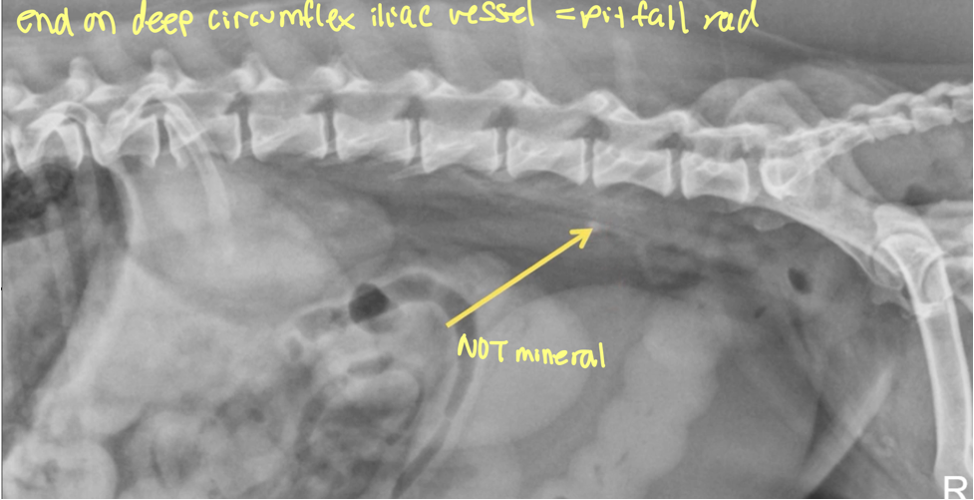

what is a structure often confused for ureteral mineral (PITFALL)

end on deep circumflex iliac vessel